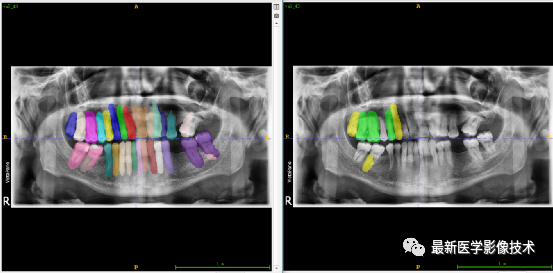

验证集牙齿分割计数和异常牙齿分割识别

左图是分割计数,右图是异常牙齿分割识别结果